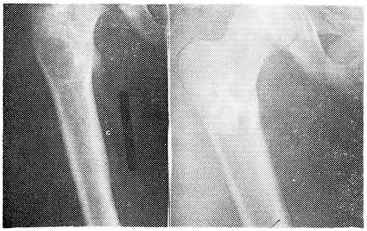

3., 15 лет, поступил в отделение 10/I 1979 г. по поводу костной кисты проксимального отдела правой бедренной кости. 24/1 под кратковременным общим обезболиванием в полость двумя иглами введено 15 мл костного микста с предварительным промыванием полости физиологическим раствором и последующим заклиниванием отверстий заостренными ксенотрансплантатами. Наложена легкая задняя гипсовая лонгета. В течение 5 дней у больного держалась субфебрильная температура. Выписан на 16-й день без гипсовой фиксации. Через 6 мес рентгенограмма показала полное замещение полости остеоидной тканью (рис. 3 и 4).

Рис. 3. Рентгенограмма больного 3. с костной кистой проксимального отдела правого бедра до и через 6 мес после пломбирования костным микстом.